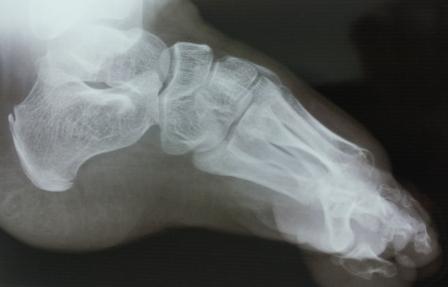

фото до лечения, после операции по Зацепину в год и операции резекции костей стопы по типу Куслика в пять лет

после 5 повязок и подкожной ахилотомии и снова гипсовой повязки на три месяца

Ребенку на фото 9 лет